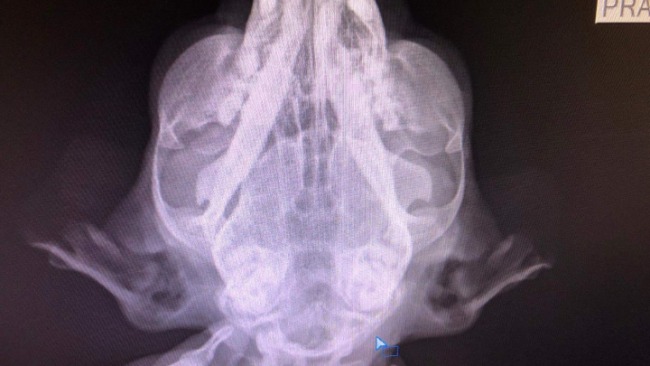

Stan kotki jest ciężki. Bati nie chodzi, ma słabe nerki i wątrobę.

Lekarz odłożył narazie operację.

Wyniki wizyty u neurologa wskazują na FIPa, dlatego chcemy podać kotce pierwszą ampułkę leku.